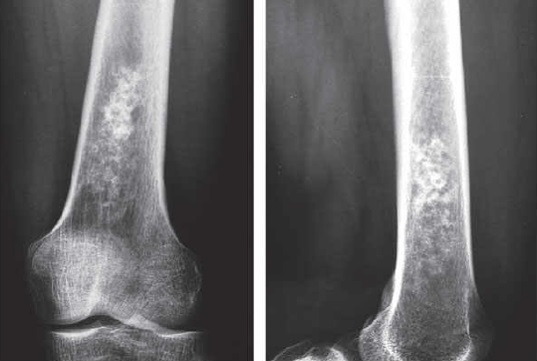

1

Q

Qual diagnóstico?

A

Lesão epifisária excêntrica

Fise aberta

dx: condroblastoma